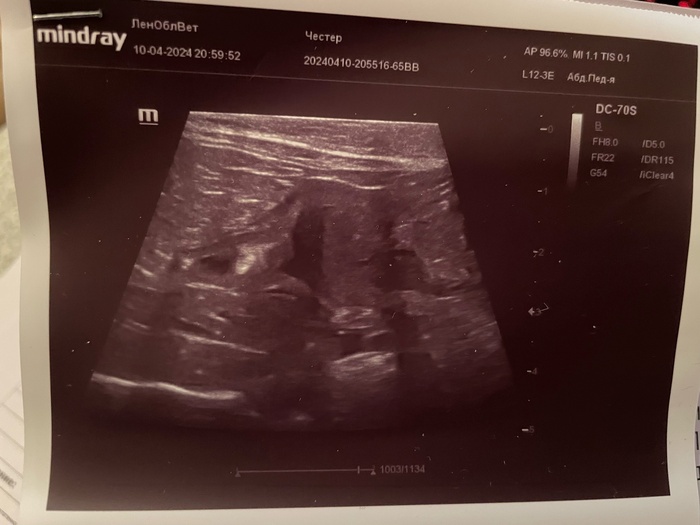

Также были назначены анализы: на электролиты, биохимия мочи, узи мочеполовой системы. Ниже в карусели прикладываю все результаты: